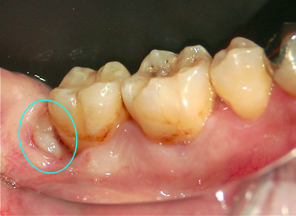

から見た写真

横向きに生える親知らずから見た写真

ちらっと見える親知らず 30代の男性。主訴は「親知らずの所に物がよく詰まる。抜歯して下さい」でした。

Dr;「親知らずは、横向きに生えていますが一部だけ見えています。この隙間を歯磨きでキレイに保つのは難しいです。食べ物が挟まったまま放置しておけば手前の歯まで虫歯になります。ガンバって抜歯を致しましょう!」